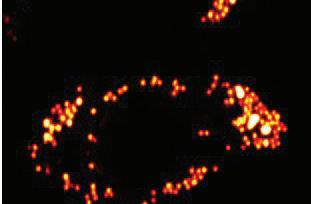

Cheng identified fatty acid saturation as the culprit using multiplex stimulated Raman scattering (SRS) imaging cytometry, a high-throughput method of single cell analysis invented in the Cheng lab.

“It’s an advanced chemical imaging tool,” says Cheng. “It provides a way to visualize a molecule—like the molecule that metabolizes fatty acids— based on the signature, the spectroscopic fingerprint of these molecules.” Instead of using dyes or fluorescent labels to image one kind of molecule, Cheng’s method reveals the bigger picture. “We can visualize fatty acids, but we can also visualize glucose, cholesterol. It gives us the opportunity to see how cancer cells metabolize, to see how they change or reprogram themselves in response to a treatment.”